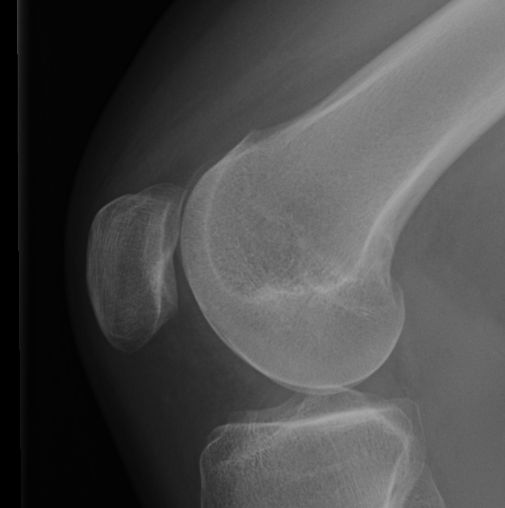

Trochlea Dysplasia / Dejour Crossover Sign

- lateral x-ray at 30o with condyles superimposed

- identify base of trochlea

- normal: clearly defined trochlea groove

- abnormal / Crossover: line of floor of trochlea crosses lateral lip of condyle

Normal trochlea / no crossover